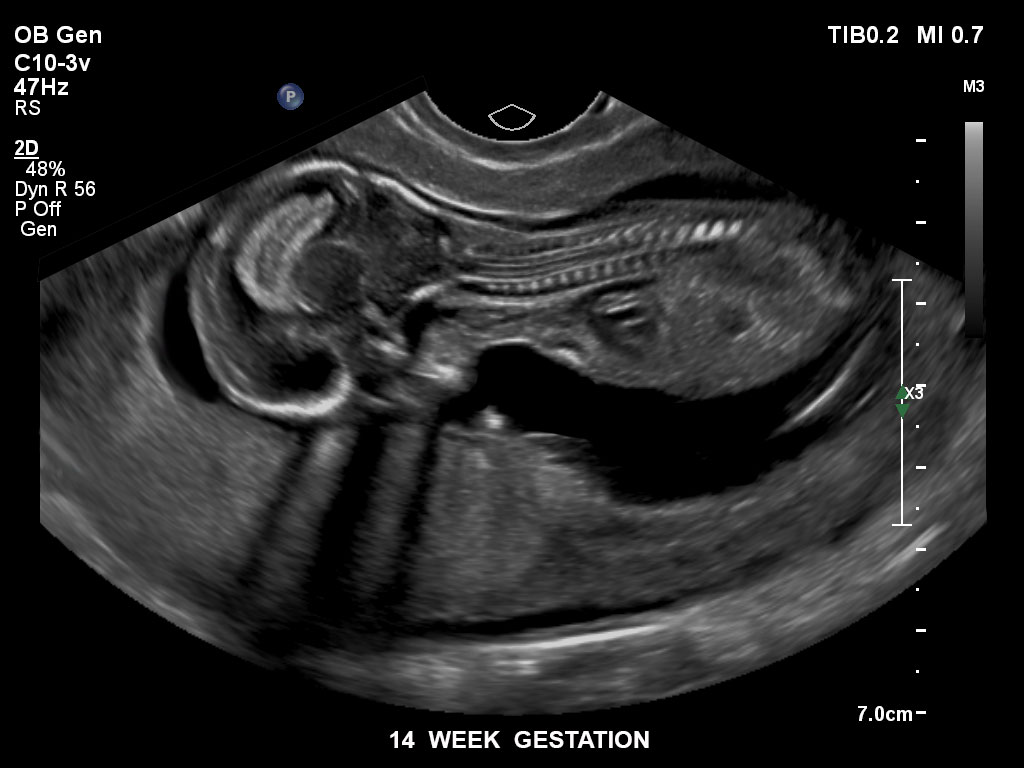

Bildgebung im 1. Trimenon

Die EPIQ-Produktreihe mit ausgereiften Schallköpfen erfüllt die Anforderungen auch Ihrer anspruchsvollsten gynäkologischen Untersuchungen und während der gesamten Schwangerschaft.

• C9-2 PureWave-Breitband-Convex-Schallkopf für Hochfrequenz-Bildgebung in der Gynäkologie und der Geburtshilfe, insbesondere für die Untersuchung im Hinblick auf mögliche Anomalien im ersten Schwangerschaftstrimester

• C10-3v PureWave-Breitband-Endo-Convex-Schallkopf, ideal für anspruchsvolle Myom- und komplexe Ovar-Untersuchungen sowie Bildgebung im ersten Schwangerschaftstrimester